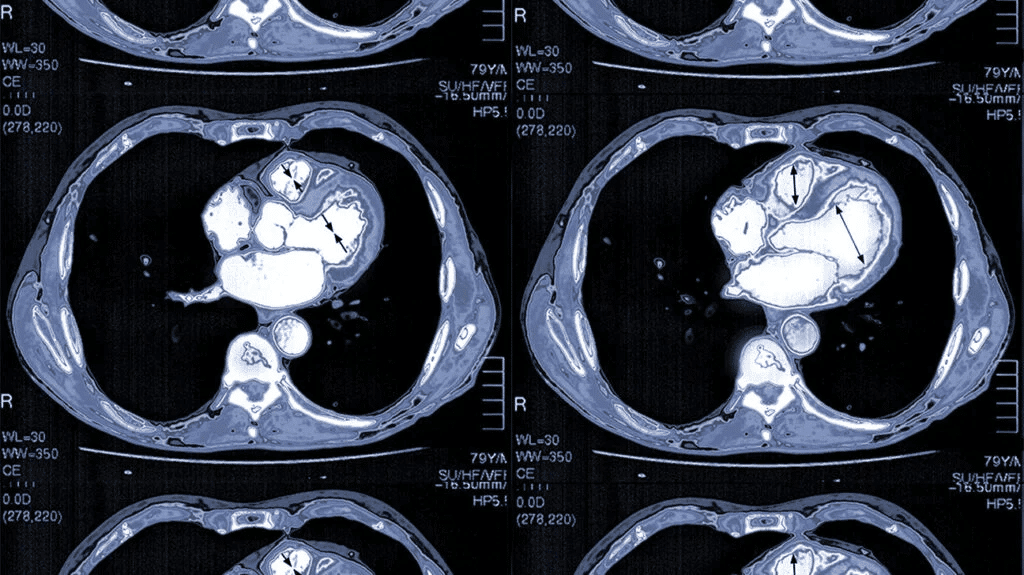

✅ 1. MRI / CT 訊號純度提升

MRI 運作於中高頻段,若周邊電子或 Wireless 訊號干擾將產生影像雜訊。

吸波材可:

• 降低 RF 模組輻射

• 改善矩陣線路耦合

有助影像更清晰並提升診斷準確度。

✔ 改善 MRI、CT、超音波成像品質